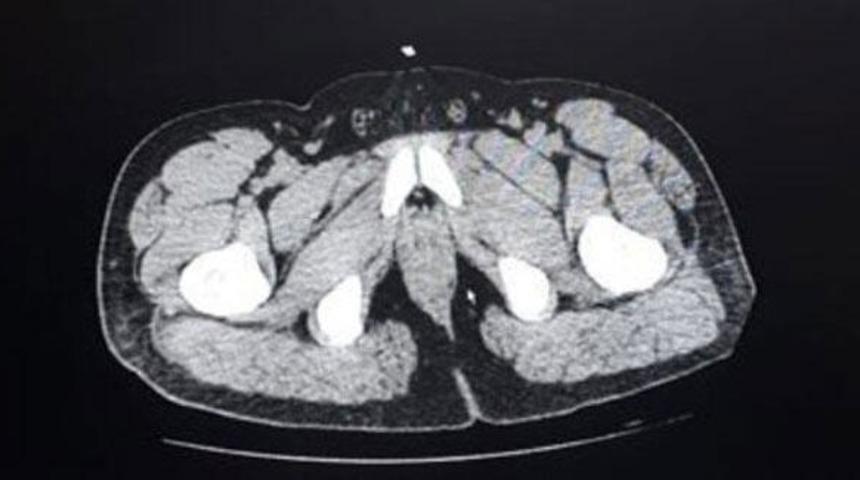

Denizli Devlet Hastanesi'ne götürülen zanlıların, uzman personel tarafından yapılan kontrollerinde, mide ve bağırsak kısımlarında yabancı madde olduğu tespit edildi.

Şüphelilerden F.D'nin 65 paket halinde 588 gram, V.D'nin ise 35 paket halinde 317 gram metamfetamini yuttuğu belirlendi. Polis kontrolünde doğal yollardan çıkarılan 100 paket halinde 905 gram metamfetamin maddesine el konuldu. Adliyeye sevk edilen 2 şüpheli, sevk edildiği adliyede tutuklandı.